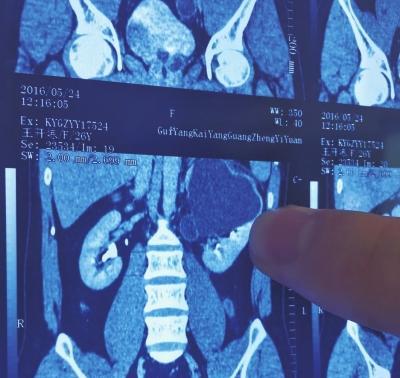

“我的丈夫有4个肾,他力气特别大!”2016年,贵州一男子精力旺盛、天生神力,白酒可以当水喝,而在面对记者时,妻子微微一笑说出了开头那句话…… 在贵州的山村里,王开炼算是个传奇人物。乡亲们提起他总会想到两件事:力气大得吓人,酒量深不见底。他从小就跟别人不一样,身子骨异常结实,精力旺盛得仿佛用不完。大冬天别人裹着棉袄还哆嗦,他却能若无其事地冲个冷水澡,一年到头也难得感冒一次。 就算偶尔磕着碰着也从不用药,似乎连休息都是多余的。王开炼的力量更是村里的一景,小时候帮父母干农活,就比同龄人顶用得多。跟伙伴们掰手腕,他从没输过;就算碰上村里混小子打群架,他一个人对付五六个也丝毫不落下风。大伙都说这小子比牛犊子还猛。 成年后为了证明自己的力气,他曾当着全家人的面,憋红了脸怒吼一声,硬生生把一个装满水、重达三百多斤的水缸抬离了地面。虽然只坚持了几秒,那画面也足以让所有人目瞪口呆。 而真正让他“一战封神”的,是2016年的一次意外。那天他父亲被一辆侧翻的摩托三轮车压住了腿,情急之下,王开炼想都没想就冲了上去,用肩膀硬是把沉重的三轮车给扛了起来,把父亲拽了出来。 他母亲起初还不信,觉得儿子只是“找对了角度”,谁知王开炼急了,大声反驳:“我就是力气大,不信我再抬一次给你看!”这才让家人彻底信了这份蛮力。至于喝酒村里人更是送他一个“千杯不醉”的绰号。据说他曾一口气喝下三斤包谷酒,第二天照样精神抖擞地开车出工。 可就是这么个铁打的汉子,也有扛不住的时候。买了货车当上司机后,他的腰开始隐隐作痛。起初他没当回事,以为是开久了落下的职业病,随便贴几张膏药就算了。谁知疼痛愈演愈烈,妻子看在眼里急在心里,硬是拖着他去了医院。 结果CT片子一出来,别说他自己,连医生都看呆了。片子上清清楚楚地显示,王开炼体内竟然有四个肾脏,左右两侧各两个。这下他那些超常的能力总算有了个看似科学的解释。多出来的肾脏,让他的代谢能力几乎是常人的一倍,难怪力气和酒量都如此惊人。 医学上把这种现象称为“双侧双肾”,极为罕见,专家推测可能与胚胎发育异常有关,甚至有种说法认为,他可能在娘胎里“吸收”了自己的双胞胎兄弟。进一步看他的家族似乎也印证了某种遗传上的独特性:他的父亲和奶奶都有六根手指,家族里也出过双胞胎。 不过这份“天赐的礼物”,早就暗中标好了价格。拥有四个肾脏,并不全是好事。这些多出来的器官本身就比正常的肾要小,结构也可能存在缺陷,这意味着患病风险更高。 而且超强的代谢功能让他的肝脏、肠胃等其他器官长期处于超负荷运转。更要命的是王开炼常年的豪饮,等于是在让肝和肾玩命地协同加班,早就给健康埋下了巨大的隐患。 果然这次要命的腰痛,罪魁祸首正是他左上侧的一个肾脏。由于严重的肾积水,它已经肿胀得像个发酵的馒头,必须立刻手术切除。经过四个小时的手术,医生成功取出了那个拳头大小的病变肾脏,然后语重心长地告诉他:必须彻底戒酒,否则剩下的三个肾也迟早要出问题。 戒酒对一个在贵州山村长大的男人来说,比切掉一个肾还难受。在当地酒几乎就是人情世故的血液。过年走亲戚,朋友递上酒杯,他怎么推?村里办酒席,没了“千杯不醉”的王开炼,气氛都淡了几分。他也试过用茶水蒙混过关,却总被乡亲们开玩笑说“不像个男人”。 内心挣扎了几个月,面对根深蒂固的酒文化和自己的习惯,王开炼最终还是下了决心。为了家人,也为了自己剩下的三个肾,这个杯不能再端了。从此酒桌上他总是端着茶杯,笑呵呵地指着自己的腰对劝酒的人说:“可不敢了,三个肾也得省着用!” 他开始学着研究健康食谱,家里的饭菜变得清淡,院子里多了几盆绿植,养的鸡也格外肥壮。妻子小丽看着丈夫的转变,欣慰地对记者说:“他还是那个天生神力的男人,只是现在更懂得惜福了。” 王开炼的故事很快传开,甚至登上了贵州的省报。有人羡慕他,觉得他该去当超级英雄;也有人看得通透:“四个肾又怎么样?还不是得悠着点活。”当地卫健部门甚至拿他的案例做起了健康宣传,告诫大家:天生的本钱再厚,也经不起肆意挥霍。 王开炼的经历像一个生动的寓言,提醒着每一个人:身体的特异功能并不等于一张健康的无限透支卡。人生就像山间的溪流,重要的不是初始水量有多大,而是懂得如何细水长流。 那么身体天赋异禀,究竟是为所欲为的资本,还是一份需要加倍小心呵护的责任呢?王开炼用自己的前半生和后半生,给出了答案。 信源链接:http://news.cnr.cn/native/gd/20160619/t20160619_522439237_1.shtml